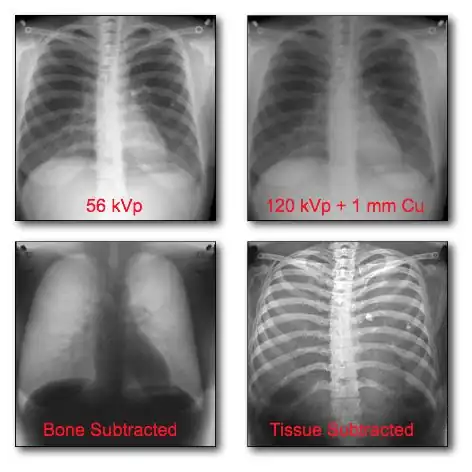

This form of image data processing is illustrated in the following figure:

A chest radiograph acquired at 56 kVp is shown in the top left panel of the figure. This is referred to as a low energy image. In the top right panel is a radiograph of the same patient's chest acquired at a high energy – 120 kVp, with 1 mm copper filtration. Results of the dual-energy processing are shown on the bottom row. The bone-subtracted image is shown in the bottom left panel and the tissue-subtracted image in the bottom right panel. Notice that the tissue-subtracted image demonstrates that the lesion in the patient's left lung is a calcified nodule, since it doesn't appear in the bone-subtracted image.